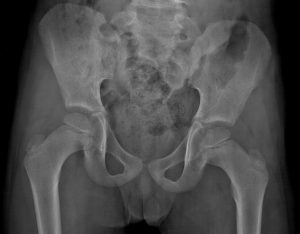

Тазобедренный сустав также может вовлекаться в воспалительный процесс, чаще это не типичная локализация. Процесс проявляется болью, синовитом, хромотой, нередко пациенты отмечают воспаление в других суставах: кисти, коленные, локтевые, лучезапястные.